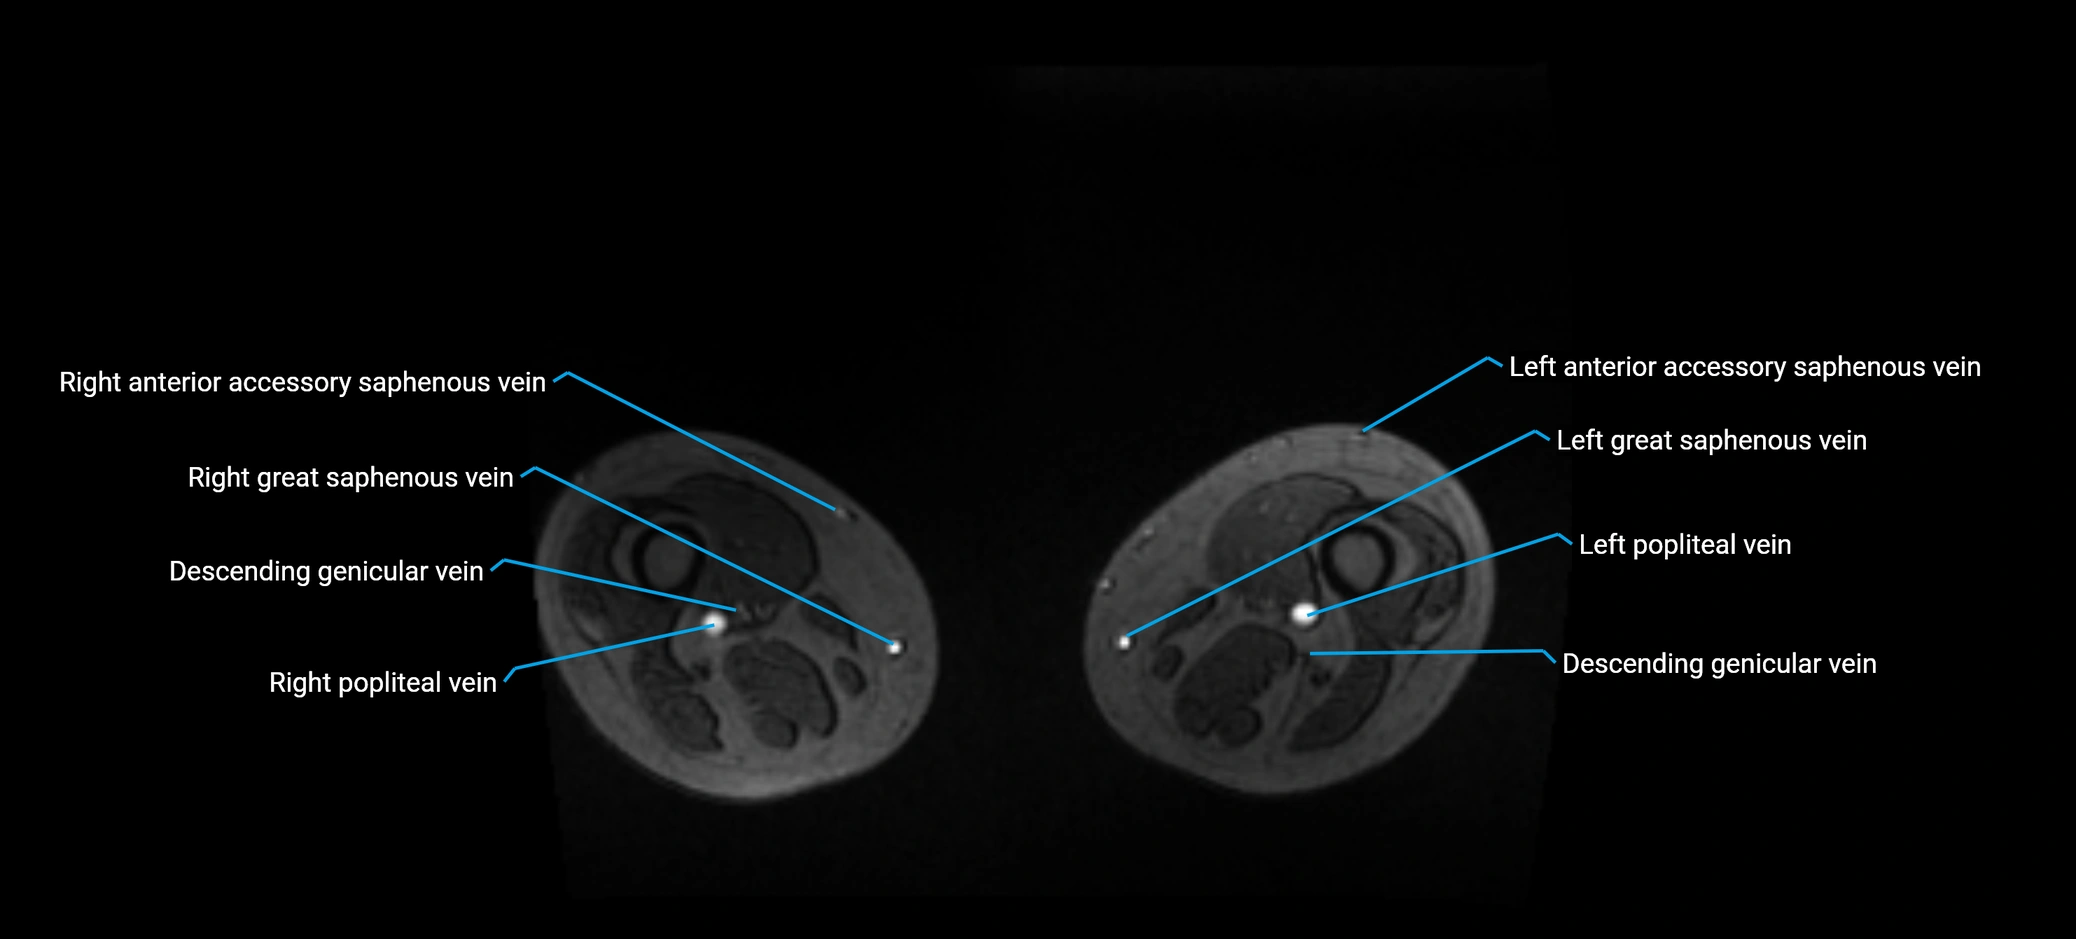

MRI image

image